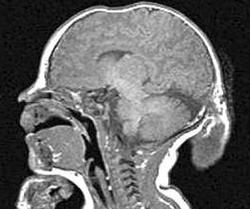

Менингоэнцефалоцеле

Назофронтальное менингожнцефалоцеле.

Энцефалоцеле

Энцефалоцеле

Передняя мозговая грыжа

Энцефалоцеле